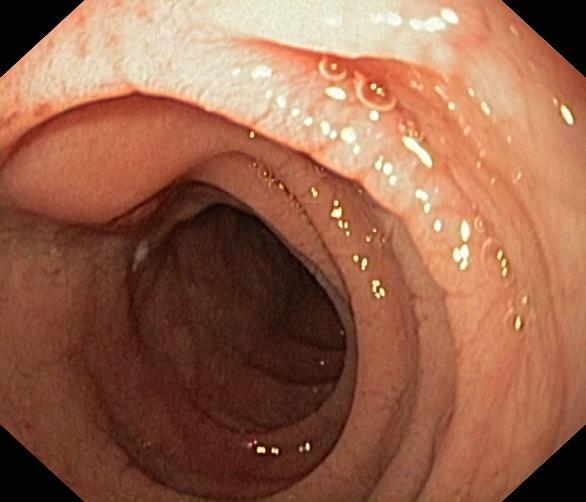

Celiakia